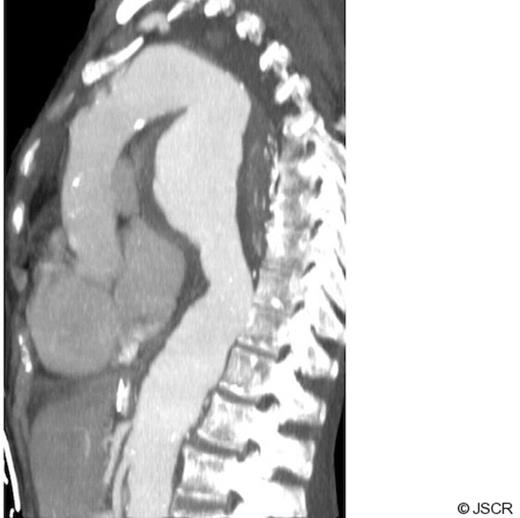

CT scanning revealed a large descending thoracic aortic aneurysm measuring 8 cm in maximum diameter (Fig 2). The left main bronchus was compressed between the aneurysm and the aortic trunk (Fig 3). The patient was regarded as unfit for an open replacement of the aneurysm. The neck of the aneurysm was markedly conical immediately distal to the left subclavian artery, so proximal stent graft placement would have necessitated left common carotid artery and left subclavian artery bypass grafting to provide a parallel proximal landing zone. The distal neck was also markedly conical with a diameter of 42 mm at the coeliac axis, with extensive mural thrombus. These features rendered a successful endovascular repair unlikely, and therefore endovascular interventional was discounted.

CT chest showing complete compression of left main bronchus by large aortic aneurysm